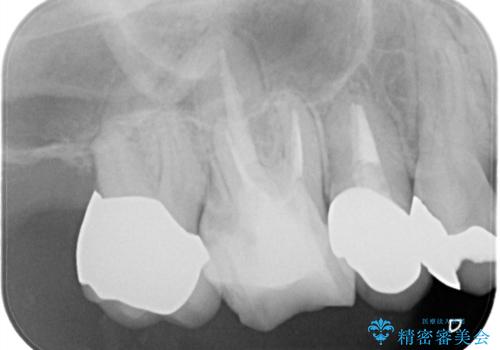

メタルボンドクラウンによる虫歯の治療

- 定期検診にて虫歯を見つけ、メタルボンドクラウンにて修復補綴治療を行なっております。

歯肉縁下まで虫歯が進行していたため歯周外科を併用して治療を行なっております。

メタルボンドクラウンは内側に金属のフレーム、外側にセラミックを使用した被せ物です。